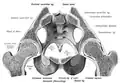

Основу таза образуют две тазовые кости, крестец и копчик, соединённые суставами пояса нижних конечностей в костное кольцо, внутри которого образуется полость, заключающая внутренние органы. До возраста 16—18 лет кости (подвздошная, лобковая и седалищная) соединены хрящами. Впоследствии происходит окостенение, и указанные кости срастаются между собой, образуя тазовую кость. Также при сращении этих костей образуется вертлужная впадина (лат. acetabulum).

Парные тазовые кости спереди соединяются при помощи лобкового симфиза, а сзади прикрепляются ушковидными поверхностями к одноимённым образованиям крестца, образуя парные крестцово-подвздошные суставы. Каждая из тазовых костей в свою очередь образована тремя составляющими: подвздошной костью, седалищной костью и лобковой костью, тела которых на наружной поверхности образуют вертлужную впадину (лат. acetabulum)— суставную ямку для головки бедренной кости, с которой образуют тазобедренный сустав.